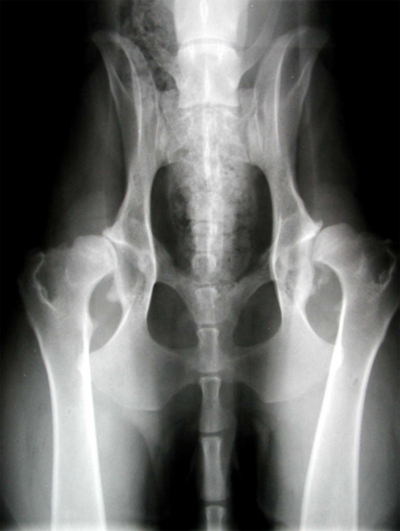

ДТБС у собак: рентгенограммы

ДТБС: степень "С" — начальная форма